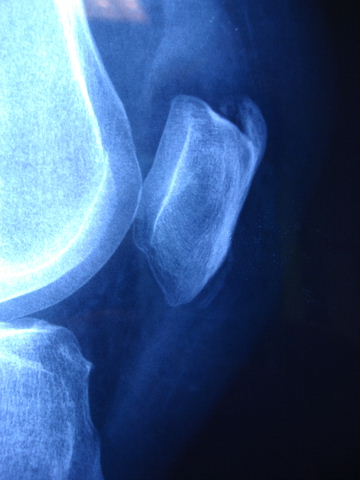

Prótesis completa de rodilla. Situación postquirúrgica. Lateral.

Prótesis completa de rodilla.Lateral.